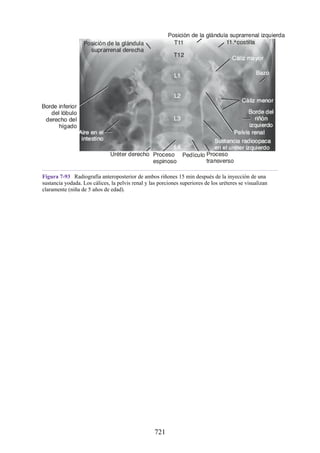

dañados, si es posible, las superficies adyacentes del ligamento dañadas se unen colocando e

inmovilizando la articulación. Algunos casos graves requieren cirugía para unir los extremos

separados del ligamento. El coágulo sanguíneo en el sitio de la lesión es invadido por vasos

sanguíneos y fibroblastos. Los fibroblastos sintetizan colágeno y fibras elásticas, que se depositan a